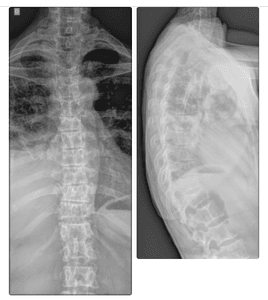

Tive câncer de mama 8 anos atrás, fiz o tratamento e tive a cura, porém precisei fazer uso de uma medicação que pode ter sido a causa de uma osteoporose grave, tornando meus ossos enfraquecidos, o que pode ter sido a causa de algumas costelas quebradas e um achatamento de uma vértebra. Além disso, apareceu nos exames um derrame pleural e será preciso fazer uma cirurgia pra descobrir a causa, que pode ser um retorno do câncer. Hoje me encontro na fila do SUS para fazer a cirurgia, pois estou desempregada e sem plano de saúde.